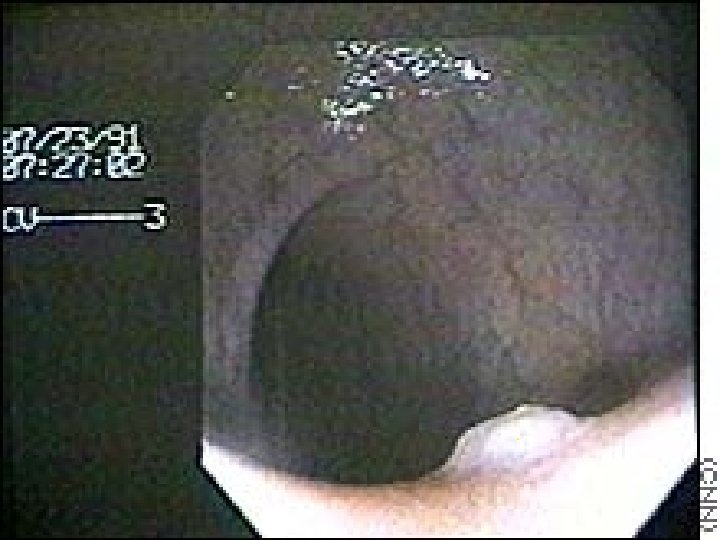

Centrální bronchiální karcinom

Obrovský invazní metastázní bronchiální karcinom

Prorůstající bronchiální karcinom

Bronchiální karcinom

Prorostlý bronchiální karcinom

Karcinom bronchu